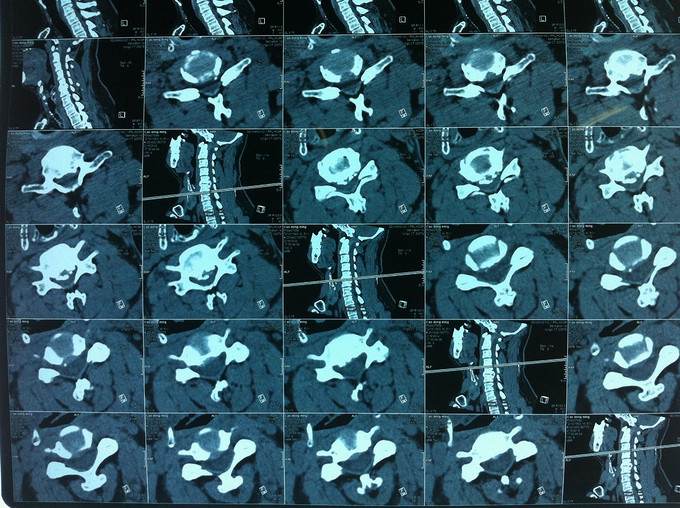

查体:颈后部压痛,颈部活动受限,双侧前臂及手感觉减退,双侧伸腕、伸肘肌肌力4级,双侧霍夫曼综合征阴性,双下肢感觉无减退,双下肢肌张力高,巴氏征可疑阳性,辅助检查: X-ray:劲椎退行性变 CT:颈椎间盘突出,腰5/6 MR:颈椎间盘突出,颈5/6节段明显